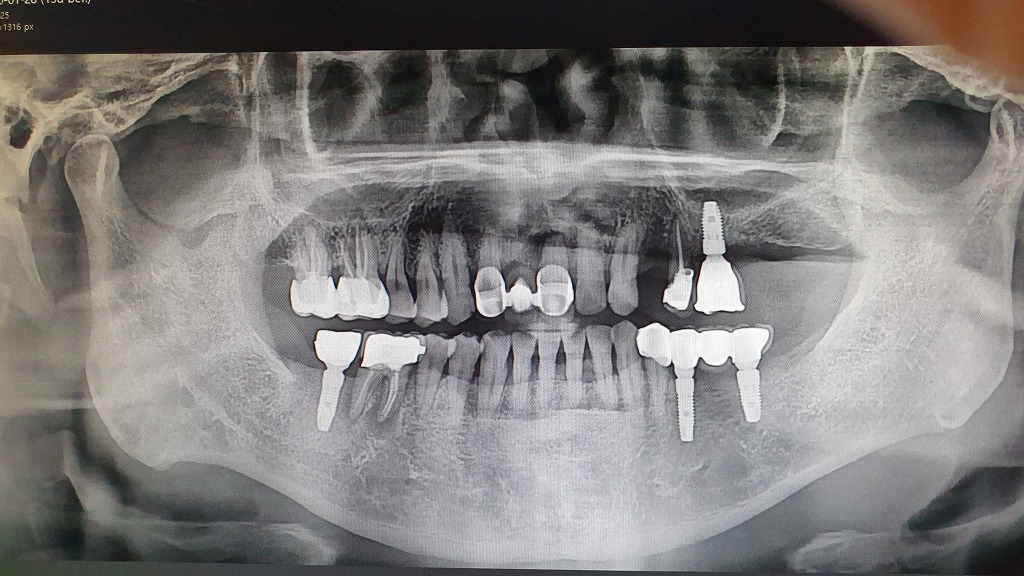

임플란트

일미치과